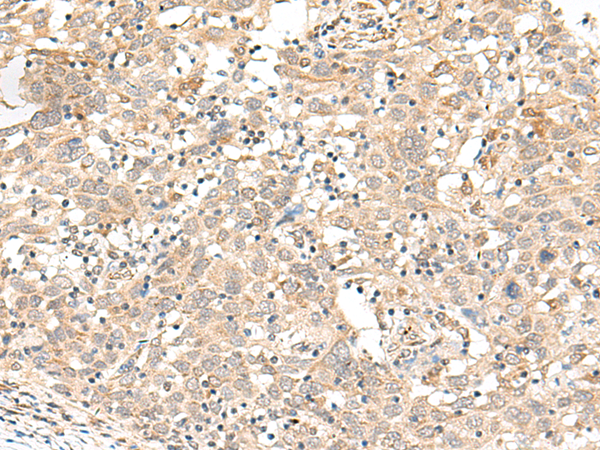

IHC positive control: |

Human cervical cancer and Human ovarian cancer |

IHC Recommend dilution: |

40-200 |